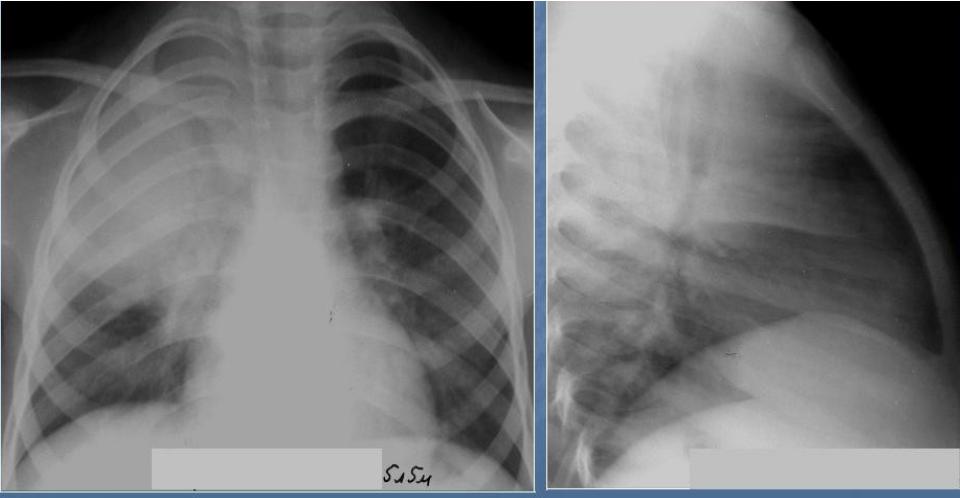

Диагностика плеврального выпота: что нужно знать